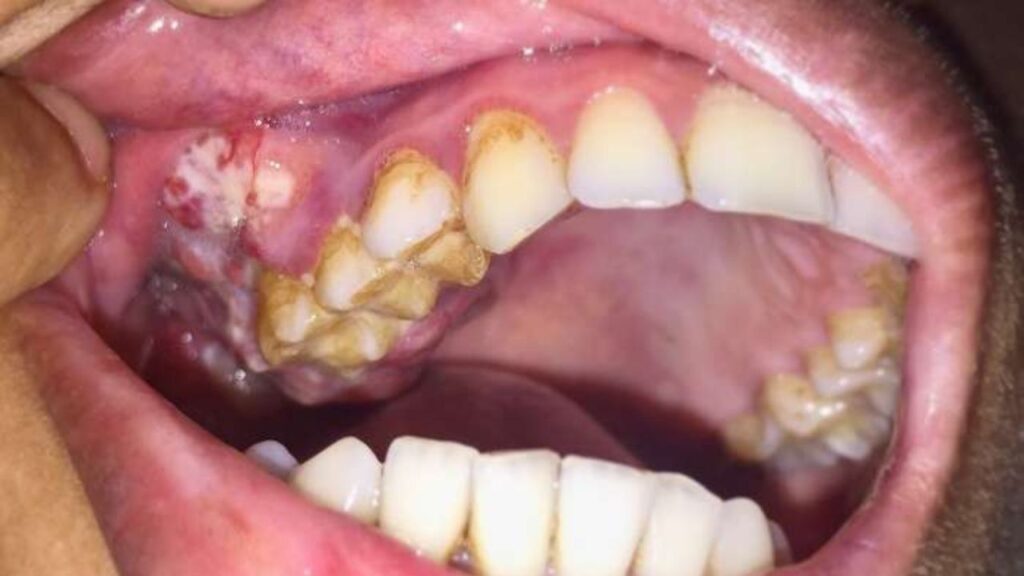

মুখের ভেতরে ছোট্ট একটি ঘা বা দাঁতের সামান্য ভাঙা অংশ—বিষয়টি আমাদের কাছে এতটাই তুচ্ছ যে আমরা প্রায়শই একে গুরুত্ব দিই না। কিন্তু আপনি কি জানেন, এই সামান্য অবহেলাই ডেকে আনতে পারে জীবনের সবচেয়ে বড় বিপর্যয়? চিকিৎসা বিজ্ঞানের ভাষায়, মুখের ভেতরে ক্রমাগত ঘর্ষণ বা Chronic Mechanical Irritation (CMI) থেকে হতে পারে ওরাল ক্যান্সার বা মুখগহ্বরর কর্কট রোগ। একটি ভাঙা দাঁত বা ঠিকমতো না বসা বাঁধানো দাঁতের (Denture) ধারালো অংশ যদি দীর্ঘ দিন ধরে আপনার গালের নরম অংশে, জিভে বা মাড়িতে আঘাত করতে থাকে এবং সেখানে ক্ষত সৃষ্টি করে, তবে সেই ক্ষত একসময় ম্যালিগন্যান্ট বা ক্যান্সারে রূপ নিতে পারে। বিশ্ব স্বাস্থ্য সংস্থা (WHO) এবং টাটা মেমোরিয়াল সেন্টারের মতো শীর্ষস্থানীয় প্রতিষ্ঠানগুলো বারবার সতর্ক করছে যে, তামাক সেবন না করেও শুধুমাত্র এই যান্ত্রিক ঘর্ষণের কারণে মানুষ ওরাল ক্যান্সারে আক্রান্ত হচ্ছে।

অধিকাংশ মানুষ মনে করেন, শুধুমাত্র বিড়ি, সিগারেট, গুটখা বা তামাকজাত দ্রব্য সেবনের ফলেই মুখের ক্যান্সার হয়। এটি একটি বড় ভুল ধারণা। যদিও তামাক প্রধান কারণ, কিন্তু একমাত্র কারণ নয়। যখন একটি ভাঙা দাঁতের ধারালো অংশ বা শার্প এজ (Sharp Edge) ক্রমাগত জিভ বা গালের ভেতরের মিউকোসা (Mucosa) বা নরম চামড়ায় ঘষা খেতে থাকে, তখন সেখানে একটি দীর্ঘস্থায়ী ক্ষতের সৃষ্টি হয়।

চিকিৎসা পরিভাষায় একে বলা হয় ‘Traumatic Ulcer’। শরীরের স্বাভাবিক নিয়ম অনুযায়ী যেকোনো ক্ষত ৭ থেকে ১০ দিনের মধ্যে সেরে যাওয়ার কথা। কিন্তু দাঁতের খোঁচা যদি সেই ক্ষতস্থানে প্রতিদিন লাগতে থাকে, তবে ক্ষতটি শুকানোর সুযোগ পায় না। দীর্ঘদিনের এই প্রদাহ বা ইনফ্ল্যামেশন কোষের ডিএনএ (DNA) কাঠামো পরিবর্তন করে দেয়, যা শেষ পর্যন্ত Squamous Cell Carcinoma (SCC) বা ওরাল ক্যান্সারে রূপান্তরিত হয়।

| স্পর্শ অনুভূতি | নরম থাকে। | ঘা-এর চারপাশ শক্ত (Indurated) এবং উঁচু হয়ে যায়। |

| রক্তপাত | সাধারণত রক্তপাত হয় না। | সামান্য স্পর্শেই রক্তপাত হতে পারে। |

| রঙ | মাঝখানে হলুদ বা সাদাটে এবং চারপাশে লাল বর্ডার থাকে। | লাল ও সাদার মিশ্রণ (Erythroleukoplakia) বা ধূসর রঙের হতে পারে। |